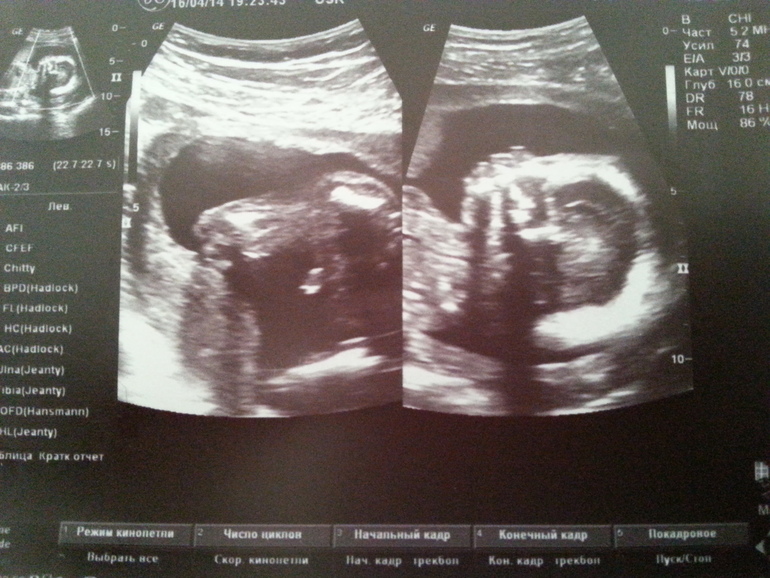

Ну и наши фоточки с УЗИ.

Слава богу, у нас все хорошо, воды в норме, плацента тоже. Головное предлежание у нас. Сердечко бьется 138 уд/м. Малыш почти все время сосал пальчик)))))) Все органы на месте, развиваются. Сейчас наша кроха весит примерно 340 гм. Сначала была съемка 2 д, а потом она переключила на 3 д. Она потом нам фотки распечатала и на диск все записала, даже с видео. Вообщем я лежала, закусив губу, чтобы не расплакаться))))) Конечно, это непередаваемые эмоции!!!!!! Мы когда вышли после УЗИ, мне хотелось летать и порхать, как бабочка!!!!! Даже не знаю, что еще написать.......самое главное, что малыш развивается правильно и с ним все хорошо!!!!